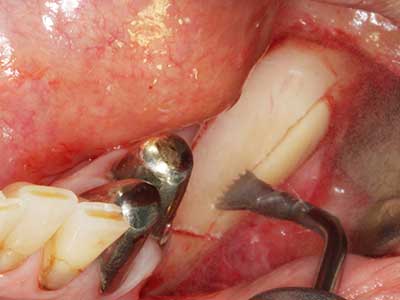

En la extracción de bloques óseos la piezocirugía también presenta ventajas adicionales: Además de la alta precisión en la osteotomía que ya se ha descrito antes, se ha comprobado que el uso de los delgados insertos de sierra resulta especialmente cuidadosas con el hueso. Frente a esto, sobre todo cuando se usan las fresas de Lindemann, cabe esperar pérdidas en la extracción significativamente más altas debido al mayor grosor de la parte frontal del cabezal (Lakshmiganthan, Gokulanathan et al. 2012). La separación basal que se necesita en particular en los injertos de bloque extraídos de forma retromolar se ve facilitada mediante sierras perpendiculares especialmente previstas a tal fin, lo que permite considerar que la cirugía piezoeléctrica es un procedimiento preciso y seguro para la obtención de bloques de hueso en el área retromolar (Happe 2007) (fig. 1-12).